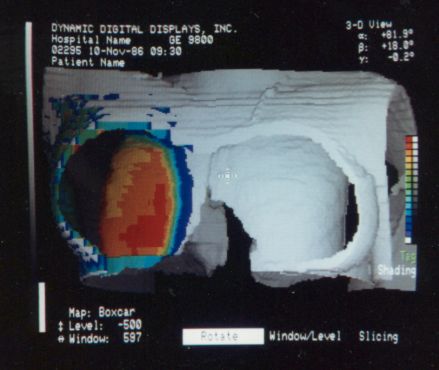

These photos of the Voxelscope II screen are typical of the types of rendering provided by the system.

Voxelscope II Screen Shots. Combination of 3-D Shaded Surface, Multiplanar Reformatting, and Segmentation